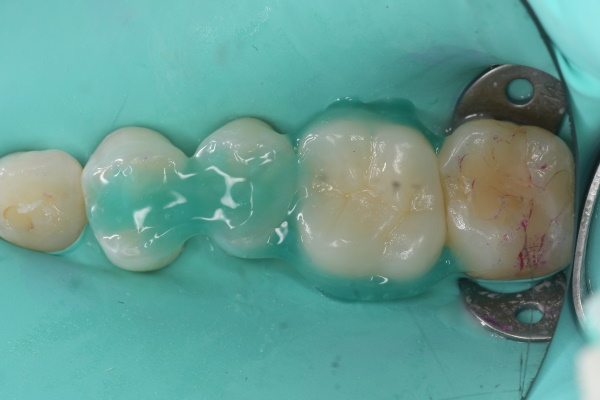

セラミック治療の治療例です。虫歯になった歯を、見た目もきれいに治したいとのご希望で来院されました。当院にて、3本同時にセラミックによる修復を実施しました。染め出しにより取り残しや汚れを確認し、プラークなどを除去したうえでセラミックを装着しています。オキシガードは、過酸化物と還元剤による化学重合反応により、歯科接着用レジンセメント表面の未重合層を硬化させる材料です。さらに、未重合層を空気から遮断することで確実な硬化を促します。接着効率をあげるためにラバーダムを使用し治療を行っております。

オキシガード使用後